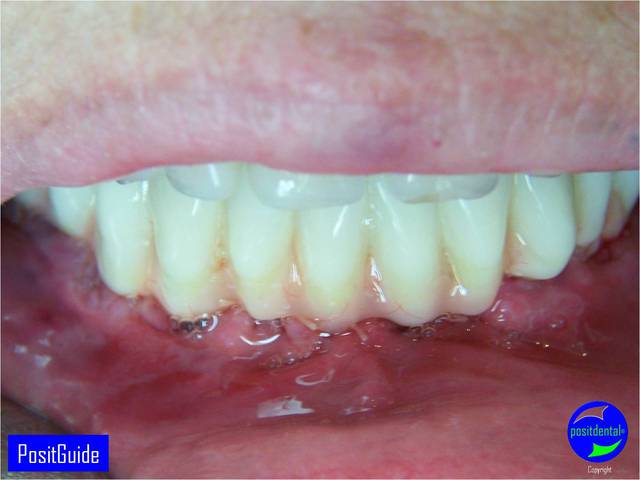

Mise en Charge Immédiate Post Extractionnelle , MCIPE partie chirurgicale de A à Z

il est en résine